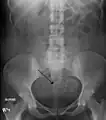

A very large (9 cm) fibroid of the uterus which is causing pelvic congestion syndrome as seen on CT